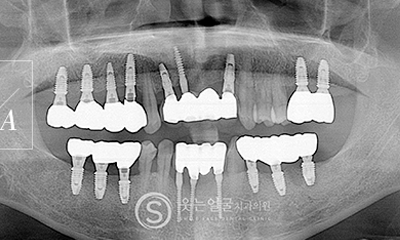

While the initial implant procedure is crucial, revision surgery may sometimes be necessary due to issues such as incorrect placement,infection, or bone loss.

SMILE FACE DENTAL CLINIC leverages extensive clinical experience and precise diagnostic equipment to accurately identify the causes of problems with existing implants and to perform safe, systematic revision procedures.

Implant

Before & After Photos